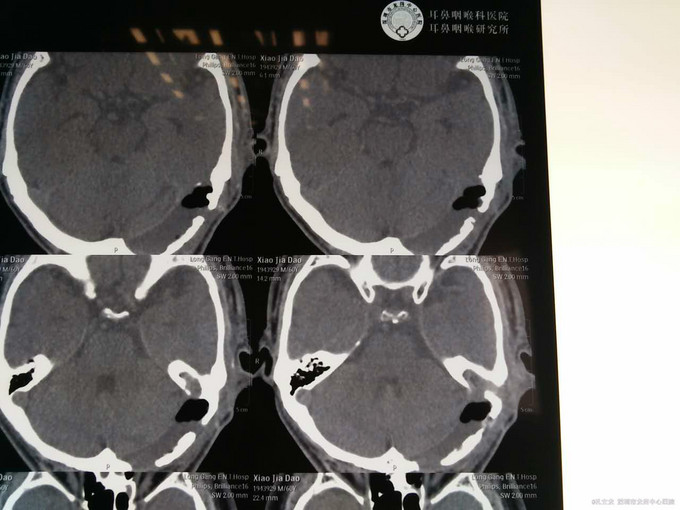

诊断:自发性颅内积气(张力性) 入院后予以完善相关检查,行颞骨乳突薄层CT扫面,考虑乳突气房内耳道漏气,粘膜瓣形成张力性气颅,再次开路手术创伤大,联合耳鼻喉科,行颅外手术,耳后入路磨除乳突气房,发现粘膜活瓣样活动,分辨漏气口,自取皮下筋膜,及带蒂肌皮瓣,填塞漏口及乳突气房,生物胶粘合,手术顺利,术后恢复良好。

患者恢复良好,术后未见皮下积气复发,复查头颅CT提示颅内积气明显吸收好转。对于此类自发性颅内积气,乳突气房与外界相通可能性大,开路手术创伤大,且效果不明显,联合耳鼻喉科手术效果明确,多学科合作在某些疾病的诊断及处理上非常重要。 颅内自发积气较少见,处理上的一点经验,跟大家一起分享,谢谢大家批评指教!